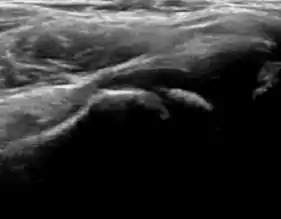

Figure 12:

Normal ultrasound appearance of the femoral head-neck junction.

Joint effusion in transient synovitis of the hip.

Flattening of the femoral head in a patient with Perthes disease.

Step in the femoral head-neck junction in a patient with SCFE.